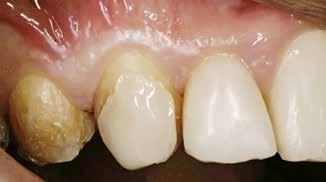

PATIENTTILFÆLDET

En 40 år gammel mand henvendte sig med bekymring for både æstetik og symptomer fra tænderne (Fig. 1). Han fortalte, at

Præoperativ status

Fig. 1. 40-årig sund og rask mand møder bekymret for sine slidte tænder. Klinisk ses frakturer og substanstab langs incisalkanterne på overkæbetænderne.

Fig. 1. A 40-year-old healthy man is concerned for his worn teeth. Clinically, fractures and loss of tooth substance are observed at the incisal edge of the upper front teeth.

Okklusalt billede af A) over- og B) underkæbe

2. Klinisk ses tydelig slitage ind i dentinen på samtlige tænder fra 6’er til 6’er i begge kæber.

Fig. 2. Clinically, extensive wear into the dentin of all teeth in both jaws is observed.

han de seneste år havde mærket, at tænderne var blevet kortere og mere takkede, og han mærkede isninger ved indtagelse af kolde drikke. Han oplyste, at han i mange år havde drukket coca-cola dagligt, og at han skar tænder. Ellers var han sund og rask, og han havde normal salivaproduktion.

Klinisk undersøgelse viste et tandsæt med enkelte restaureringer, men med slitagedefekter okklusalt/incisalt på samtlige tænder fra 6’er til 6’er i over- og underkæbe (Fig. 2). Defekterne strakte sig tydeligt ind i dentinen. Baseret på anamnesen og de kliniske fund blev erosion set som hovedårsagen til tandsliddet, mens attrition formodedes at være en medvirkende faktor.